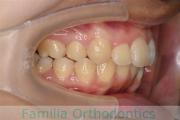

No.22V-029

- 叢生

- 上顎前突

- 19歳

- 男性

- 上:

- 8448

- 下:

- 主な使用装置:

- FEA 022

- 治療にかかった費用:

- 92万円

でこぼこを治したいということで来院されました。上下左右から親知らずも第一小臼歯も抜歯が必要で、歯科矯正アンカースクリューを併用して大臼歯を後ろに引っ張りながらの治療でした。3年弱、35回程度の通院が必要でした。

叢生が著しく、後戻りのリスクがあります。またアンカースクリューが必須のため、もしもスクリューが安定しないと、治療が難しく長くなってしまう恐れがありましたが、幸い脱落は見られませんでした。